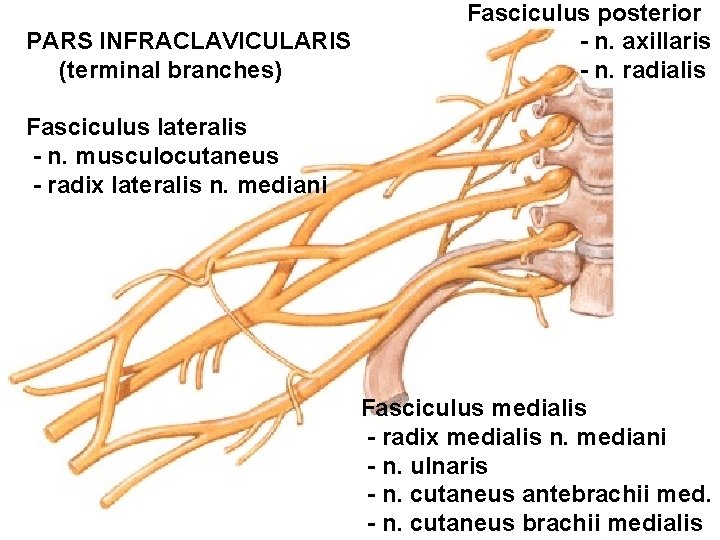

Pars infraclavicularis plexus brachialis - fasciculus medialis - fasciculus lateralis - fasciculus posterior

PARS INFRACLAVICULARIS (terminal branches) Fasciculus posterior - n. axillaris - n. radialis Fasciculus lateralis - n. musculocutaneus - radix lateralis n. mediani Fasciculus medialis - radix medialis n. mediani - n. ulnaris - n. cutaneus antebrachii med. - n. cutaneus brachii medialis